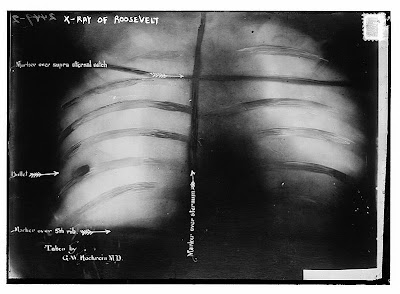

X-Ray of Roosevelt's ribcage showing the bullet at lower left

While campaigning in Wisconsin on October 14, 1912 a saloonkeeper named John Schrank shot him in the chest. The bullet passed through Roosevelt’s metal eyeglass case and 50 sheets of paper before entering his chest. Roosevelt believed that because he was not coughing blood he did not need to go to the hospital immediately. He mounted the podium and gave a 90 minute speech, all the while blood seeping from the wound. His opening words were "Ladies and gentlemen, I don't know whether you fully understand that I have just been shot; but it takes more than that to kill a Bull Moose."

Doctors decided against surgery and the bullet remained in his chest for the rest of his life.